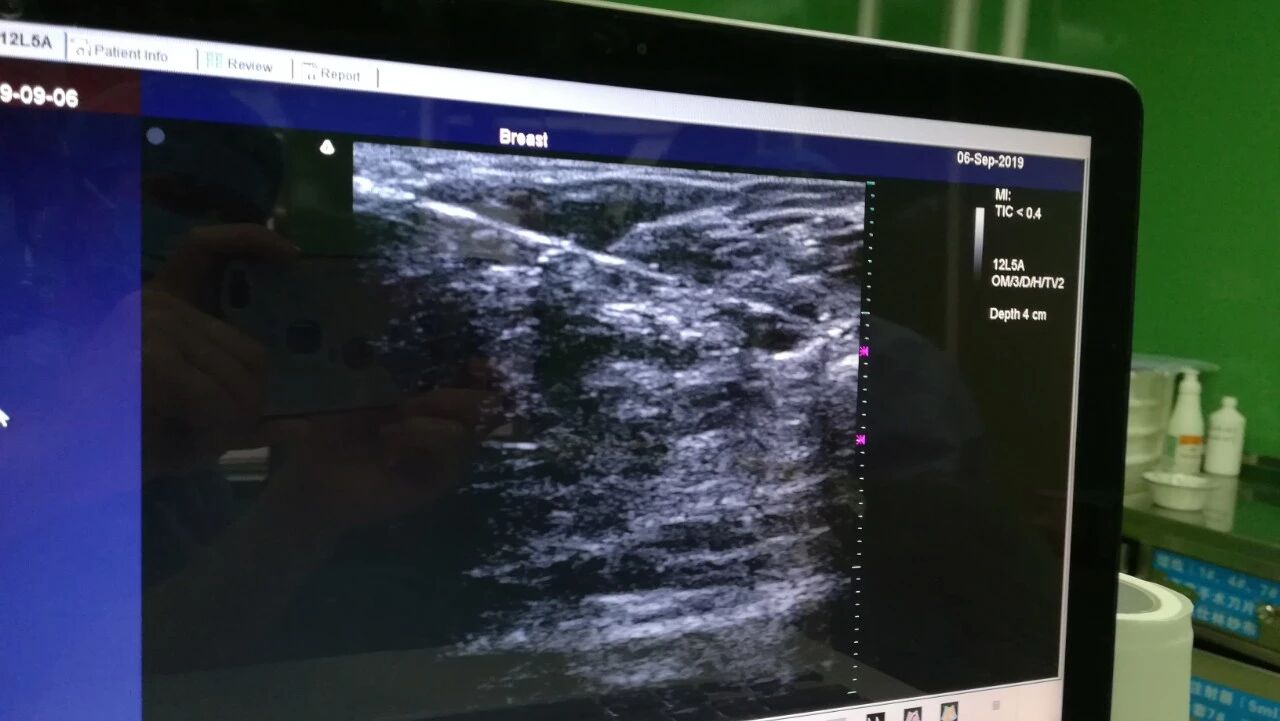

“24小时之内完成入院、手术和出院,而且治疗质量靠谱,这么快真的想不到。”尝到日间手术的甜头,陈女士一脸惊喜,说不仅节约了时间,而且家属陪护产生的各种费用以及住院花费都大为减少。据统计,广西桂东人民医院自今年6月26日正式启动日间手术以来,共完成日间手术32例。所有手术期间,均未发生严重并发症。1.需提前完善门诊检查:乳腺彩超、钼靶或甲状腺彩超、甲状腺功能等;2.经门诊医生评估可以进入日间手术后预约手术时间;3.预约的当天在9点钟之前办好住院手续,开绿色通道检查心电图、肝肾功、血凝等常规检查;5.出院评估:专科医生对患者依据PADS评分量表完成打分;满分10分,评分>=9分的患者结合实际情况可办理出院。